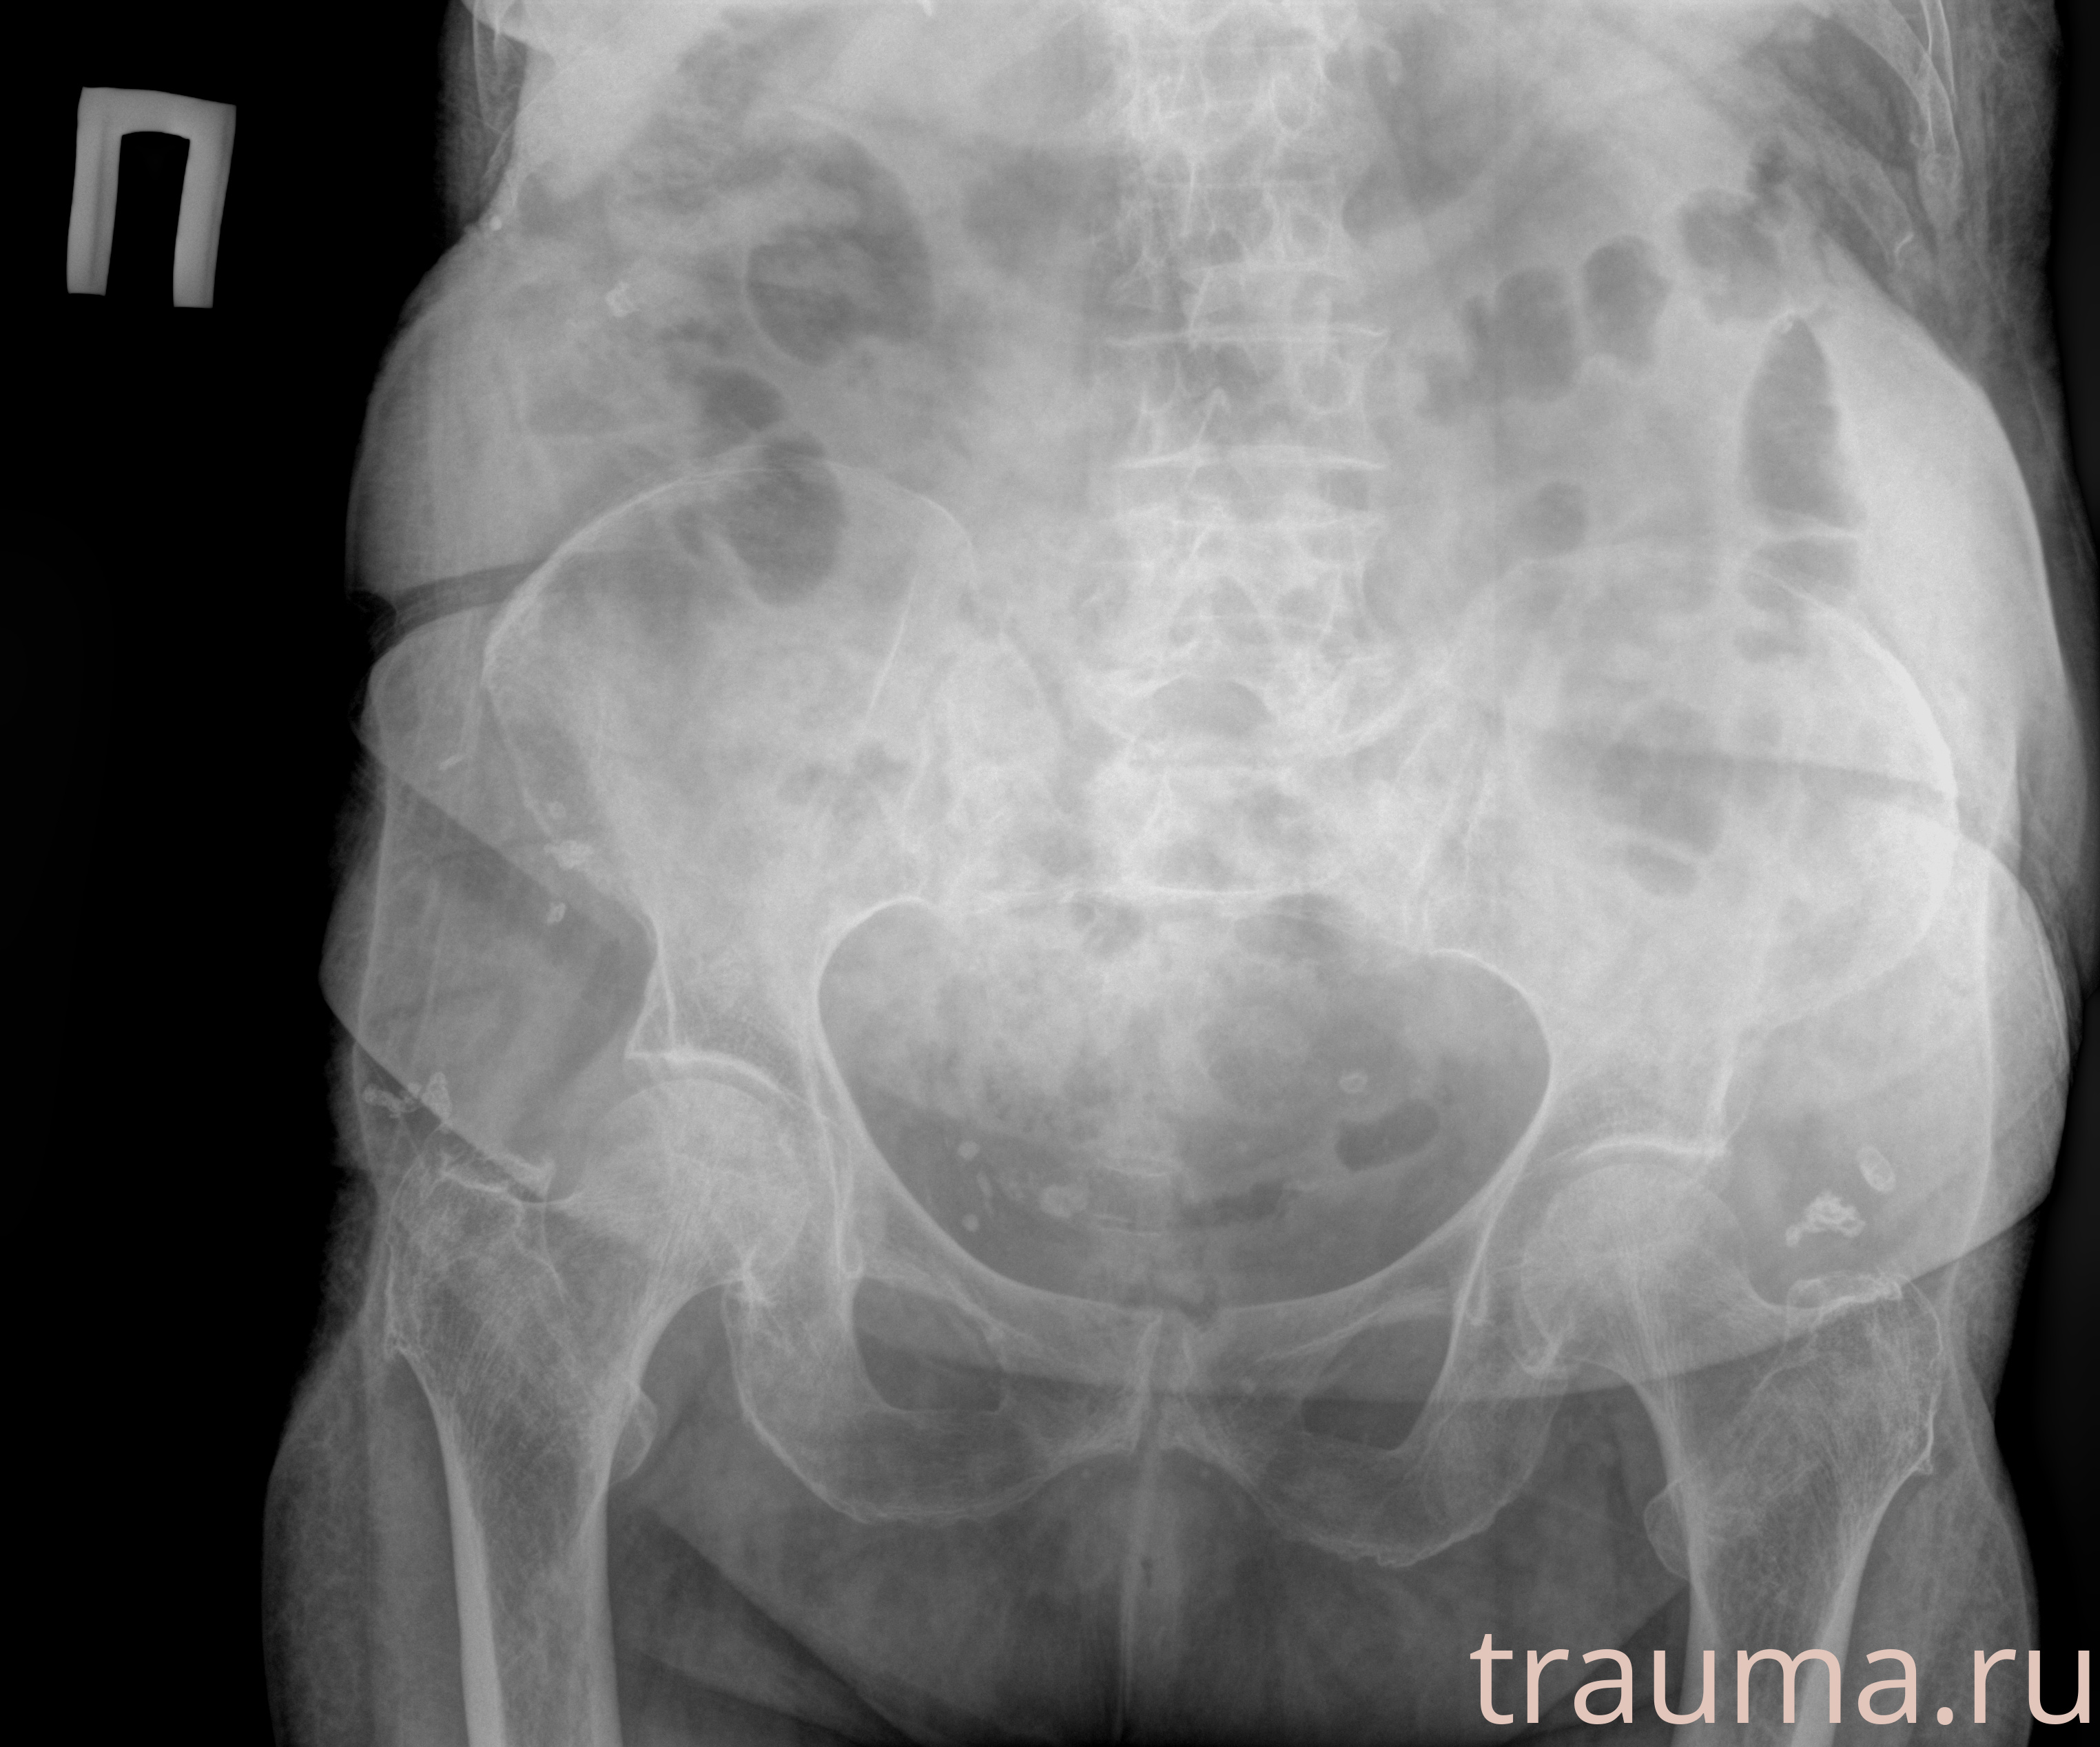

Рентген на дому: по вашему адресу приезжает врач-рентгенолог, травматолог-ортопед с мобильным рентгеновским аппаратом, проводит диагностику травмы или заболевания, делает необходимые рентгенограммы, дает рекомендации по дальнейшему лечению. Получить качественные снимки в домашних условиях возможно благодаря уникальной методике, разработанной МосРентген Центром для института  Склифосовского